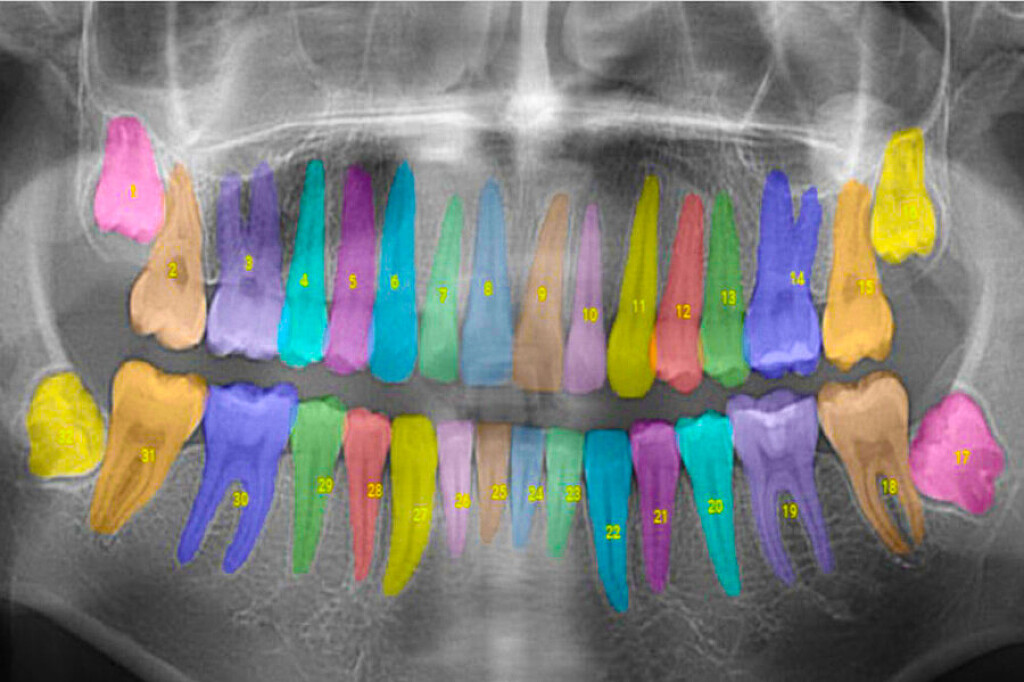

Inam is the co-founder of Overjet, a company using artificial intelligence to analyze and annotate X-rays for dentists and insurance providers. Overjet seeks to take the subjectivity out of X-ray interpretations to improve patient care.

Overjet has been cleared by the Food and Drug Administration to detect and outline cavities and to quantify bone levels to aid in the diagnosis of periodontal disease, a common but preventable gum infection that causes the jawbone and other tissues supporting the teeth to deteriorate.

In addition to helping dentists detect and treat diseases, Overjet’s software is also designed to help dentists show patients the problems they’re seeing and explain why they’re recommending certain treatments.